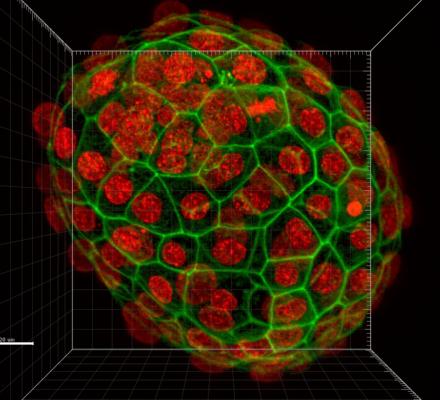

Projevy stárnutí oocytů (vajíček) je možné zvrátit a lze opravit jejich poškození. To, co bylo dosud považováno za biologicky nemožné, dokázal mezinárodní výzkumný tým vedený reprodukční bioložkou Helenou Fulkovou z Ústavu experimentální ...